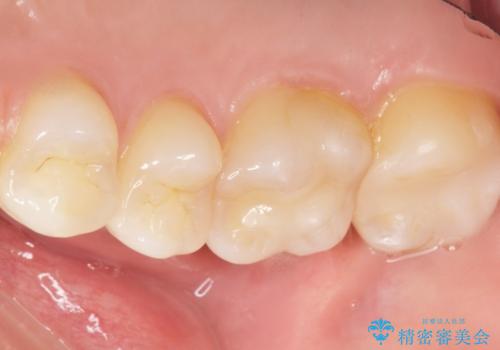

気にされていたフロスをした時のにおいがなくなり、喜んで頂けました。

治療終了後半年のメンテナンス時には「咬み合わせもばっちりです!」とおっしゃって下さいました。

インレーの種類:セラミックインレー e-max press